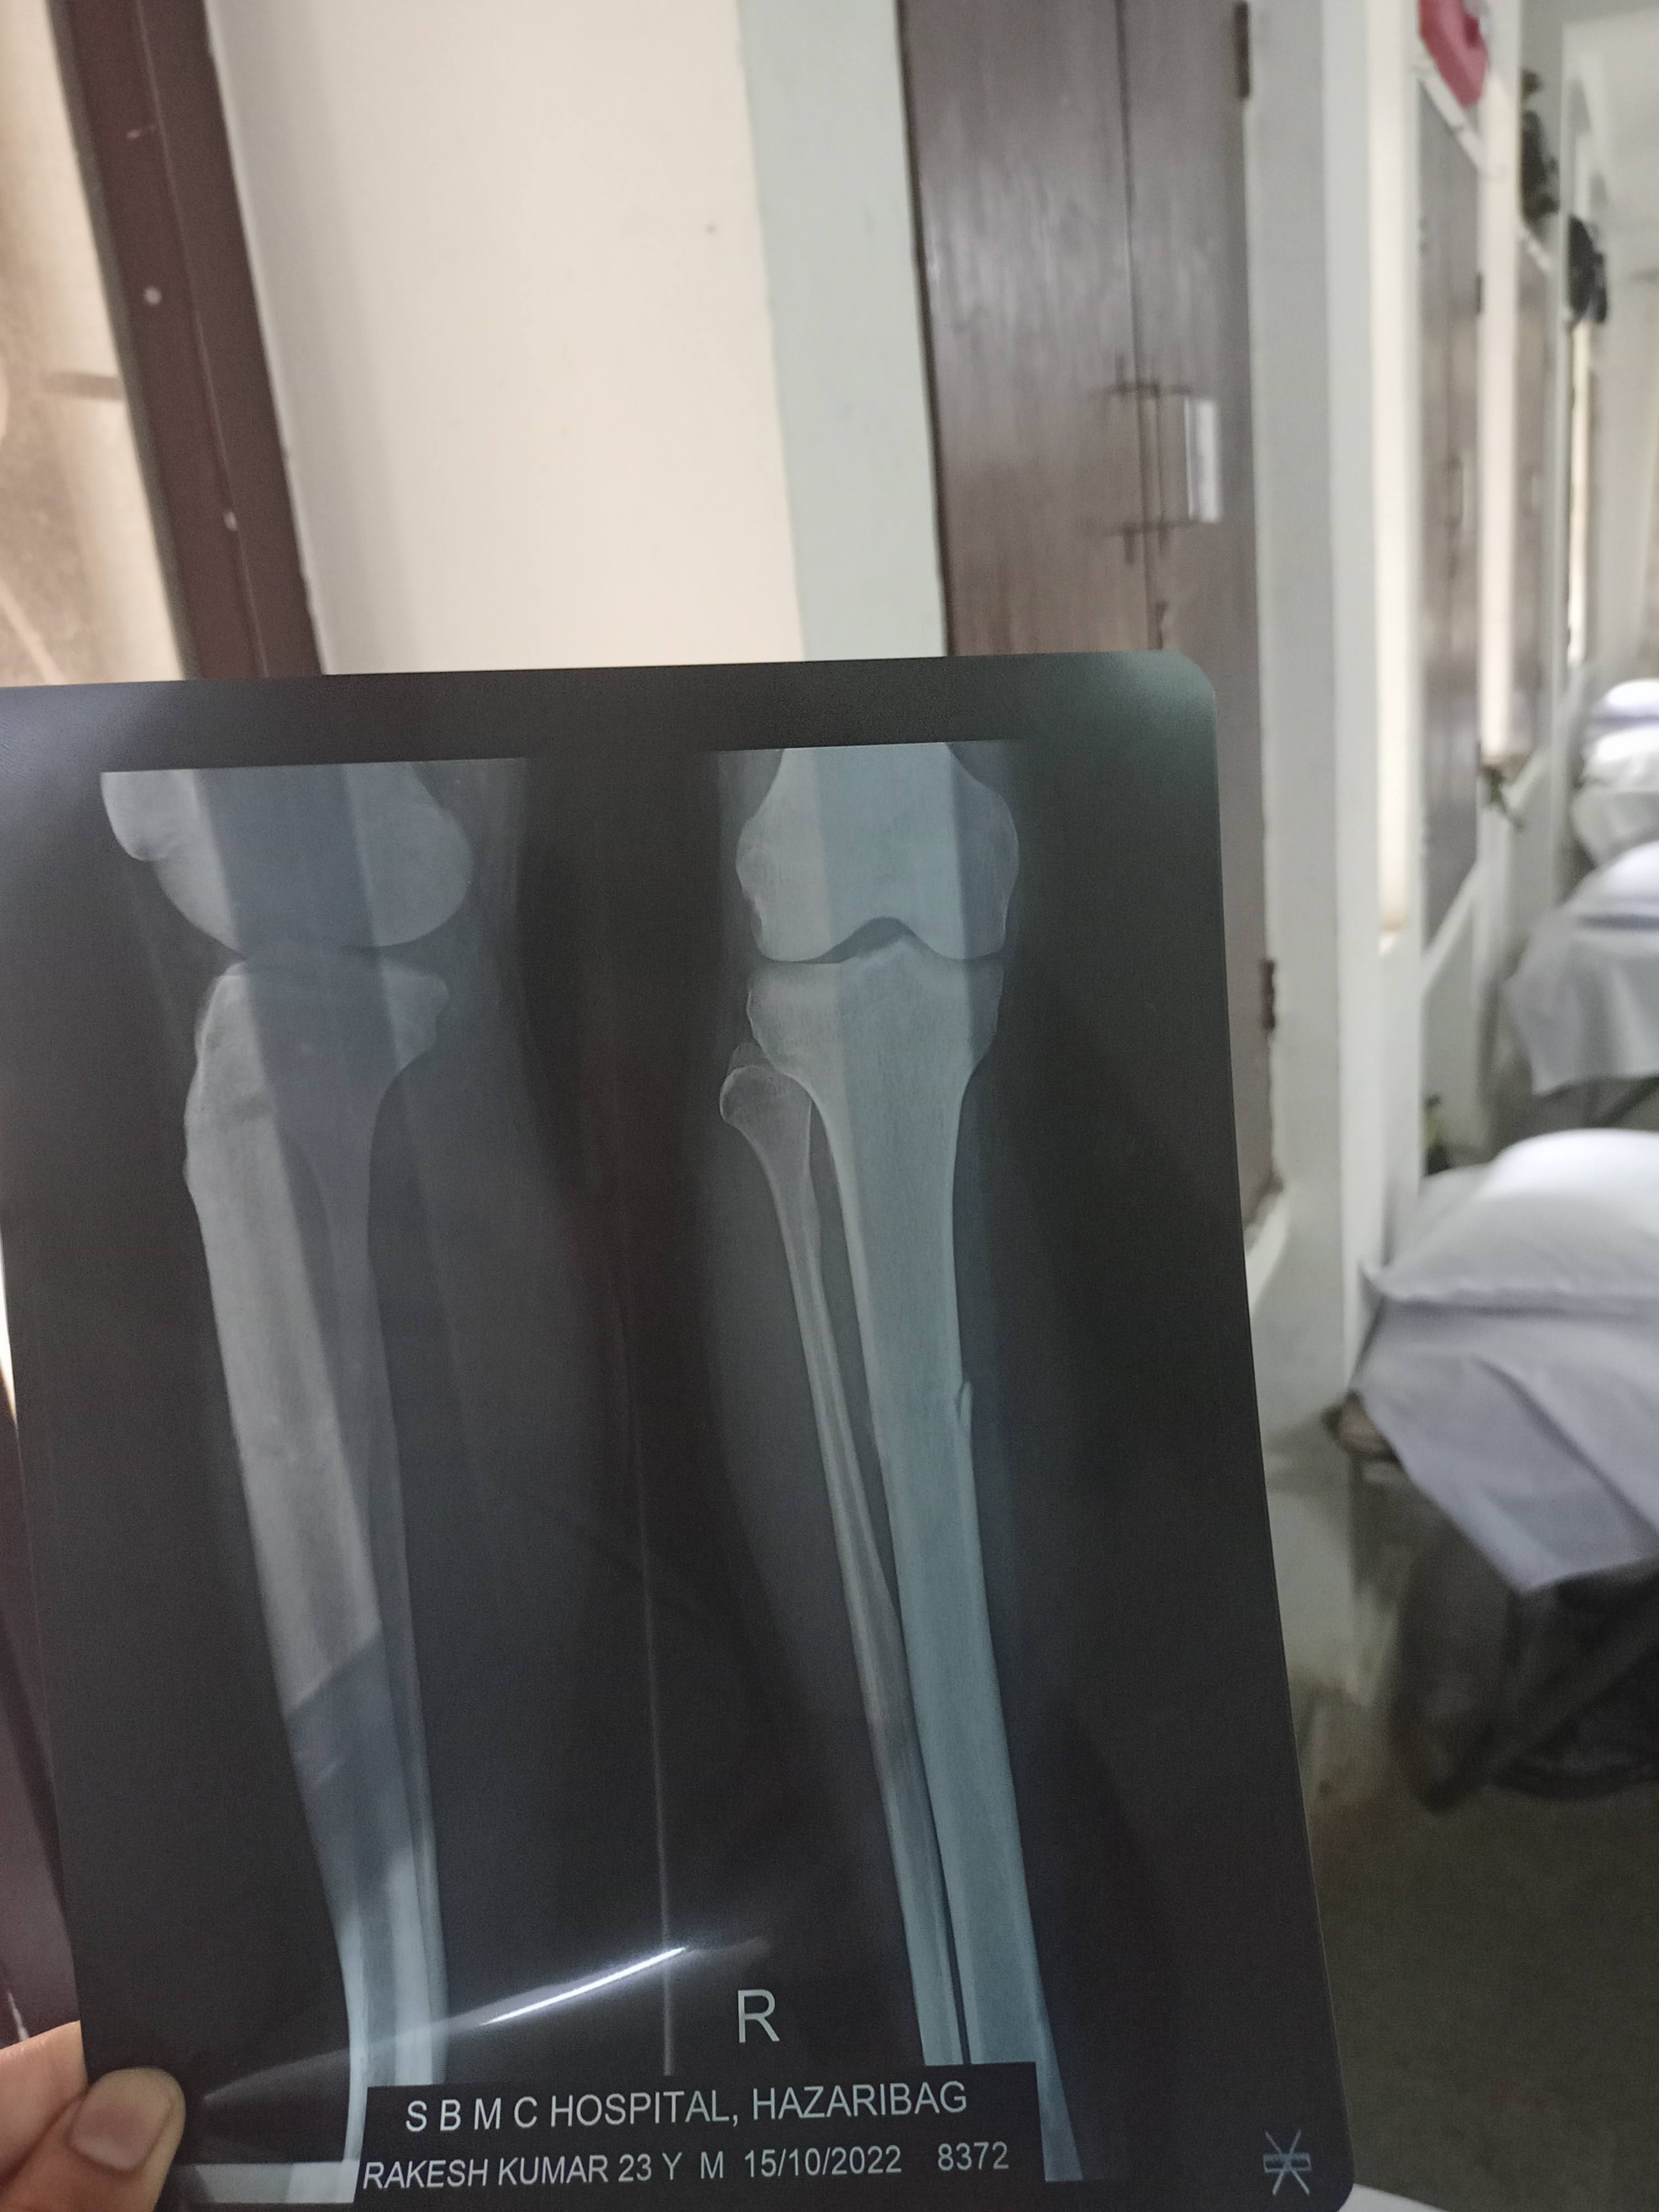

Ek month pahle Mere tibia me training k dauran fracture ho gaya

Doctor ne 4 weeks k liye kchha slab rkha abhi kchha slab htane k baad bhi fracture heal nahi hua hai

Me apni x-ray reports apko send krr rha huu plz have a look and give me suggestions regarding further treatment and speedy recovery ??